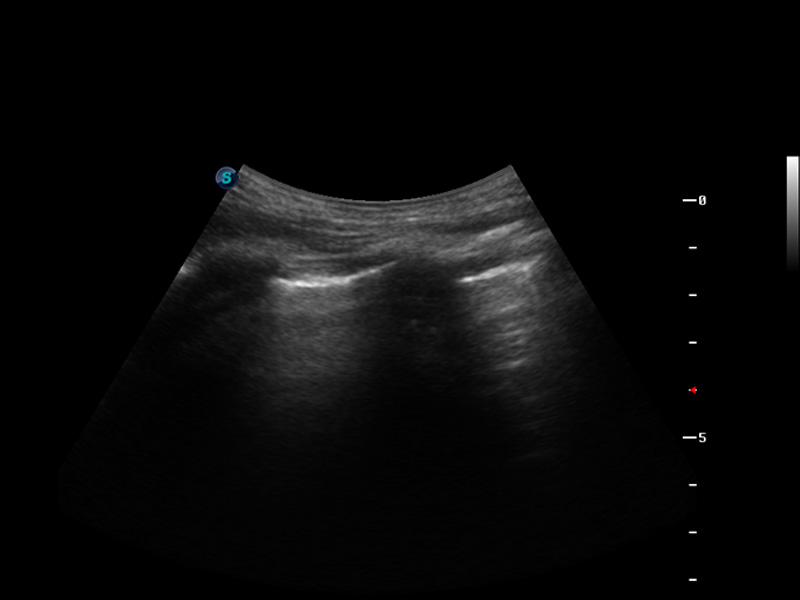

S9便携式彩色多普勒超声诊断仪是环球UG官网研发的高端便携彩超设备,外观设计新颖、产品性能卓越。S9在便携超声领域采用了突破传统的触摸屏交互设计,并以先进的软件硬件技术和设计理念,为您带来清晰的图像质量、稳定的工作性能和便捷的操作体验。

μ-Scan微米成像